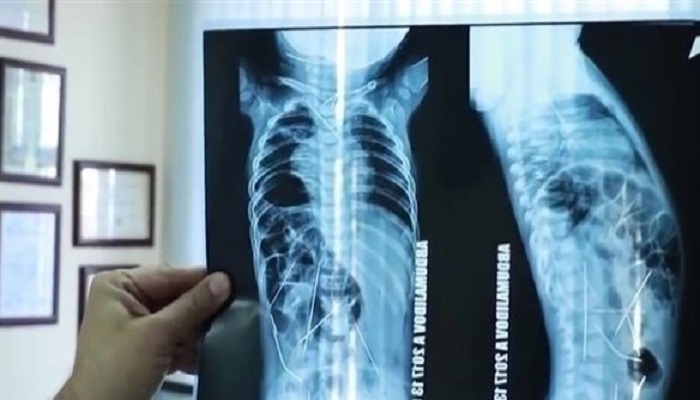

أجرى الأطباء في أوزبكستان عملية جراحية لإزالة 16 إبرة خياطة، تم العثور عليها داخل جسد طفل رضيع لا يتجاوز من العمر 11 شهراً، بعد أن عانى من ارتفاع في درجة الحرارة وصعوبة بالتبول.

وأظهرت صور الأشعة السينية، وجود 16 إبرة خياطة داخل جسد الطفل، في كل من القلب والعنق والعمود الفقري والقولون والمثانة، وذلك بعد نقله إلى المستشفى، حيث خضع على الفور لعملية جراحية عاجلة استمرت 9 ساعات، تمكن الأطباء فيها من إزالة 13 إبرة.

وخلال العملية الجراحية الدقيقة، أزال الجراحون 3 إبر من صدر الطفل، و9 أخرى من بطنه، وواحده من صدره، ومن المقرر أن يخضع لعملية جراحية أخرى، لإزالة الإبر المتبقية، والتي لا تشكل تهديداً لحياته، بحسب صحيفة ميرور البريطانية.